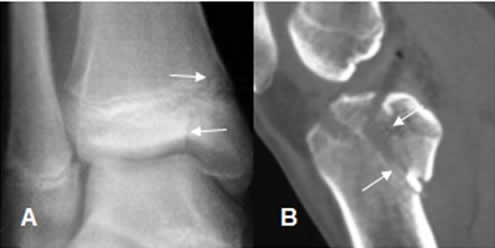

Fig 78 A. Salter tipo V.

A: Rx AP y B: Rx lateral. Disminución del espacio en la placa de crecimiento y esclerosis asociada, en el seguimiento de un deslizamiento epifisiario tipo V.